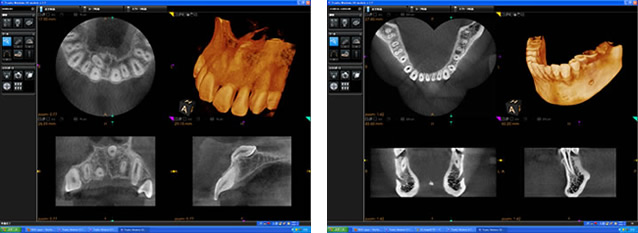

当院では、より精密な治療をするために歯科用3次元CTスキャンを導入しています。

歯科用CTスキャンのメリットとしては、通常のレントゲン写真と違い3次元での解析ができるるため、より正確に精密な診断が可能になります。また、院内にCTスキャンがあることにより、撮影⇒解析⇒診断が格段に迅速になり、患者様の負担とドクターの初期診断のスピードが速くなり、治療がより円滑に行うことができます。

歯科用CTスキャンは、インプラント治療だけでなく歯周病、根管治療、親知らずの抜歯、矯正歯科などすべての歯科治療において有効であります。そのため当院では、より正確で精密な診断をするためには歯科用3次元CTスキャンは必要不可欠と考えております。